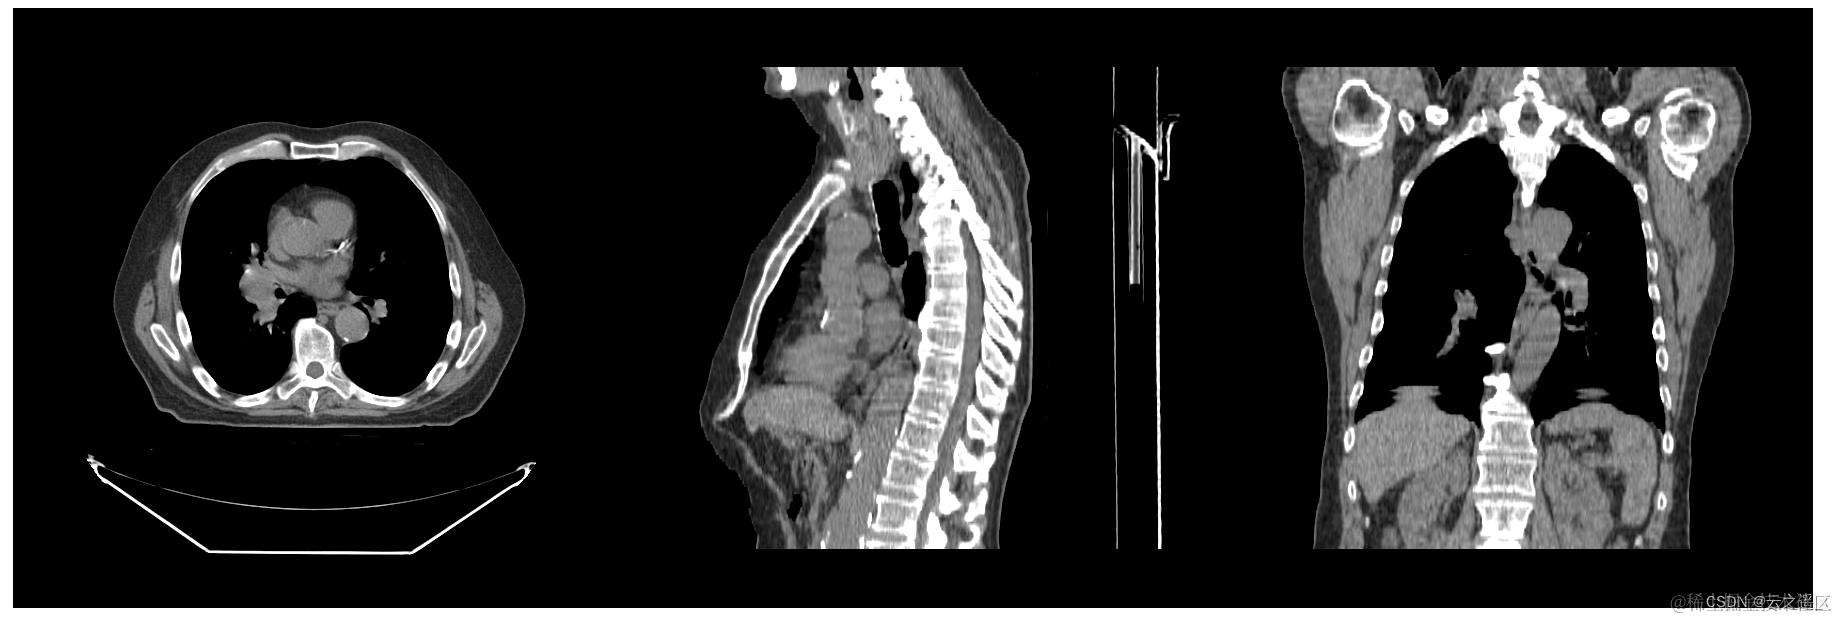

- 🎉 bingo 渲染结果